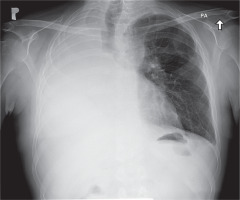

We present a case of a 43-year-old man with respiratory failure in the course of chronic dysfunction of lungs. The patient had been diagnosed with many chronic conditions, such us post-transplantation renal insufficiency, post-transplantation diabetes (PTD), exocrine pancreatic insufficiency, and osteopenia. In 2014, 4 years prior to the described events, the patient underwent lung transplantation due to the advancement and progression of cystic fibrosis. He was operated on in a different European lung transplantation center. The early and late post-transplantation periods were complicated by chronic infection with Pseudomonas aeruginosa and Pneumocystis jiroveci in 2015 and 2016. From March 2016, there was a gradual deterioration of breathing. The biopsy revealed chronic graft rejection with the BOS 1 subtype (forced expiratory volume in 1 second (FEV1) 80%); therefore, steroid therapy was administered. Six months later, the patient’s condition deteriorated, with a significant impairment of FEV1, requiring antithymocyte globulin ATG and further extracorporeal photopheresis treatment. In 2017 the patient developed oxygen-dependent respiratory failure with a rapidly decreasing FEV1 from 60% to 40%. As a consequence, the patient was successfully qualified for lung retransplantation. In October 2018, the patient underwent retransplantation of the left lung at our center. Veno-arterial extracorporeal membrane oxygenation (ECMO) with peripheral cannulation was commenced owing to the expected chest adhesions. After surgical exposure via a clamshell incision through the previous scar, the anatomical structures were difficult to identify. The preparation was started from the left lung. Because of the existing difficult anatomical conditions and thus the prolonged ischemic time for the first lung (11 hours), the transplantation of the second lung was cancelled (Figure 1). The patient was then transferred to the intensive care unit (ICU) and extubated on the third postoperative day. Due to postoperative renal failure on the first day after retransplantation, the patient required renal replacement therapy. On the 10th postoperative day, it was decided to perform pneumonectomy of the right lung, due to increasing dyspnoea and significant pulmonary leakage in the previous graft. During ICU stay, on the 17th day after retransplantation, because of the persistent postoperative bleeding into the post-resection cavity, rethoracotomy with a successful hemostatic effect was performed. The patient was discharged home on the 66th postoperative day (Figure 2). In a two-month follow-up, the patient was in a good overall condition with progressive improvement of respiratory function and FEV1.